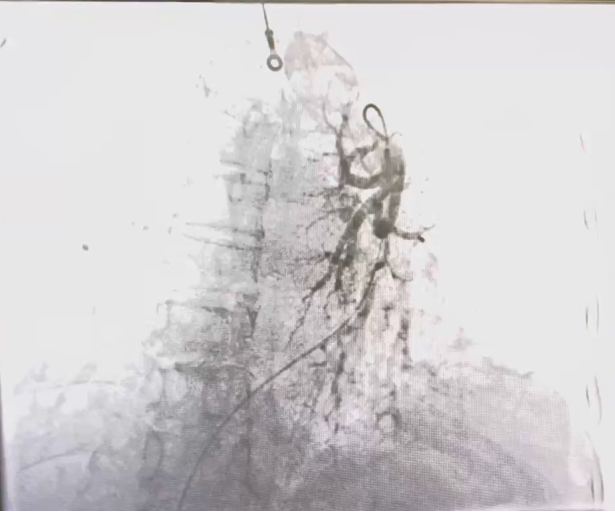

3.患者氧合指数极低,I型呼吸衰竭,持续经鼻高流量氧疗;结合患者既往病史、临床症状及辅助检查,考虑患者冠心病、全心功能衰竭,并不排除肺栓塞可能,于9月26日行冠状动脉造影术+肺动脉造影术+必要时冠状动脉内支架置入术。经过精心治疗,患者于近期好转出院。

患者行介入手术 患者造影结果